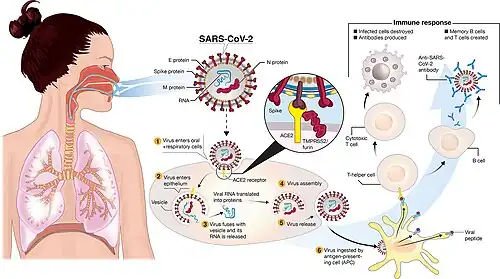

Transmission and life-cycle of SARS-CoV-2, which causes COVID-19 | |

Severe acute respiratory syndrome coronavirus 2 (SARS-CoV-2) is a novel severe acute respiratory syndrome coronavirus. It was first isolated from three people with pneumonia connected to the cluster of acute respiratory illness cases in Wuhan.[101] All structural features of the novel SARS-CoV-2 virus particle occur in related coronaviruses in nature,[102] particularly in Rhinolophus sinicus (Chinese horseshoe bats).[103]

SARS-CoV-2 is closely related to the original SARS-CoV.[106] It is thought to have an animal (zoonotic) origin. Genetic analysis has revealed that the coronavirus genetically clusters with the genus Betacoronavirus, in subgenus Sarbecovirus (lineage B) together with two bat-derived strains. It is 96% identical at the whole genome level to other bat coronavirus samples (BatCov RaTG13).[107][108][109] The structural proteins of SARS-CoV-2 include membrane glycoprotein (M), envelope protein (E), nucleocapsid protein (N), and the spike protein (S). The M protein of SARS-CoV-2 is about 98% similar to the M protein of bat SARS-CoV, maintains around 98% homology with pangolin SARS-CoV, and has 90% homology with the M protein of SARS-CoV; whereas, the similarity is only around 38% with the M protein of MERS-CoV.[110]

Pathophysiology

The SARS-CoV-2 virus can infect a wide range of cells and systems of the body. COVID‑19 is most known for affecting the upper respiratory tract (sinuses, nose, and throat) and the lower respiratory tract (windpipe and lungs).[125] The lungs are the organs most affected by COVID‑19 because the virus accesses host cells via the receptor for the enzyme angiotensin-converting enzyme 2 (ACE2), which is most abundant on the surface of type II alveolar cells of the lungs.[126] The virus uses a special surface glycoprotein called a "spike" to connect to the ACE2 receptor and enter the host cell.[127]

Multiple viral and host factors affect the pathogenesis of the virus. The S-protein, otherwise known as the spike protein, is the viral component that attaches to the host receptor via the ACE2 receptors. It includes two subunits: S1 and S2.

- S1 determines the virus-host range and cellular tropism via the receptor-binding domain.

- S2 mediates the membrane fusion of the virus to its potential cell host via the H1 and HR2, which are heptad repeat regions.

Studies have shown that S1 domain induced IgG and IgA antibody levels at a much higher capacity. It is the focus spike proteins expression that are involved in many effective COVID‑19 vaccines.[162]

The M protein is the viral protein responsible for the transmembrane transport of nutrients. It is the cause of the bud release and the formation of the viral envelope.[163] The N and E protein are accessory proteins that interfere with the host's immune response.[163]

Host factors

Human angiotensin converting enzyme 2 (hACE2) is the host factor that SARS-CoV-2 virus targets causing COVID‑19. Theoretically, the usage of angiotensin receptor blockers (ARB) and ACE inhibitors upregulating ACE2 expression might increase morbidity with COVID‑19, though animal data suggest some potential protective effect of ARB; however no clinical studies have proven susceptibility or outcomes. Until further data is available, guidelines and recommendations for people with hypertension remain.[164]

The effect of the virus on ACE2 cell surfaces leads to leukocytic infiltration, increased blood vessel permeability, alveolar wall permeability, as well as decreased secretion of lung surfactants. These effects cause the majority of the respiratory symptoms. However, the aggravation of local inflammation causes a cytokine storm eventually leading to a systemic inflammatory response syndrome.[165]

Immunity

The immune response by humans to SARS-CoV-2 virus occurs as a combination of the cell-mediated immunity and antibody production,[337] just as with most other infections.[338] B cells interact with T cells and begin dividing before selection into the plasma cell, partly on the basis of their affinity for antigen.[339] Since SARS-CoV-2 has been in the human population only since December 2019, it remains unknown if the immunity is long-lasting in people who recover from the disease.[340] The presence of neutralising antibodies in blood strongly correlates with protection from infection, but the level of neutralising antibody declines with time. Those with asymptomatic or mild disease had undetectable levels of neutralising antibody two months after infection. In another study, the level of neutralising antibodies fell four-fold one to four months after the onset of symptoms. However, the lack of antibodies in the blood does not mean antibodies will not be rapidly produced upon reexposure to SARS-CoV-2. Memory B cells specific for the spike and nucleocapsid proteins of SARS-CoV-2 last for at least six months after the appearance of symptoms.[340]